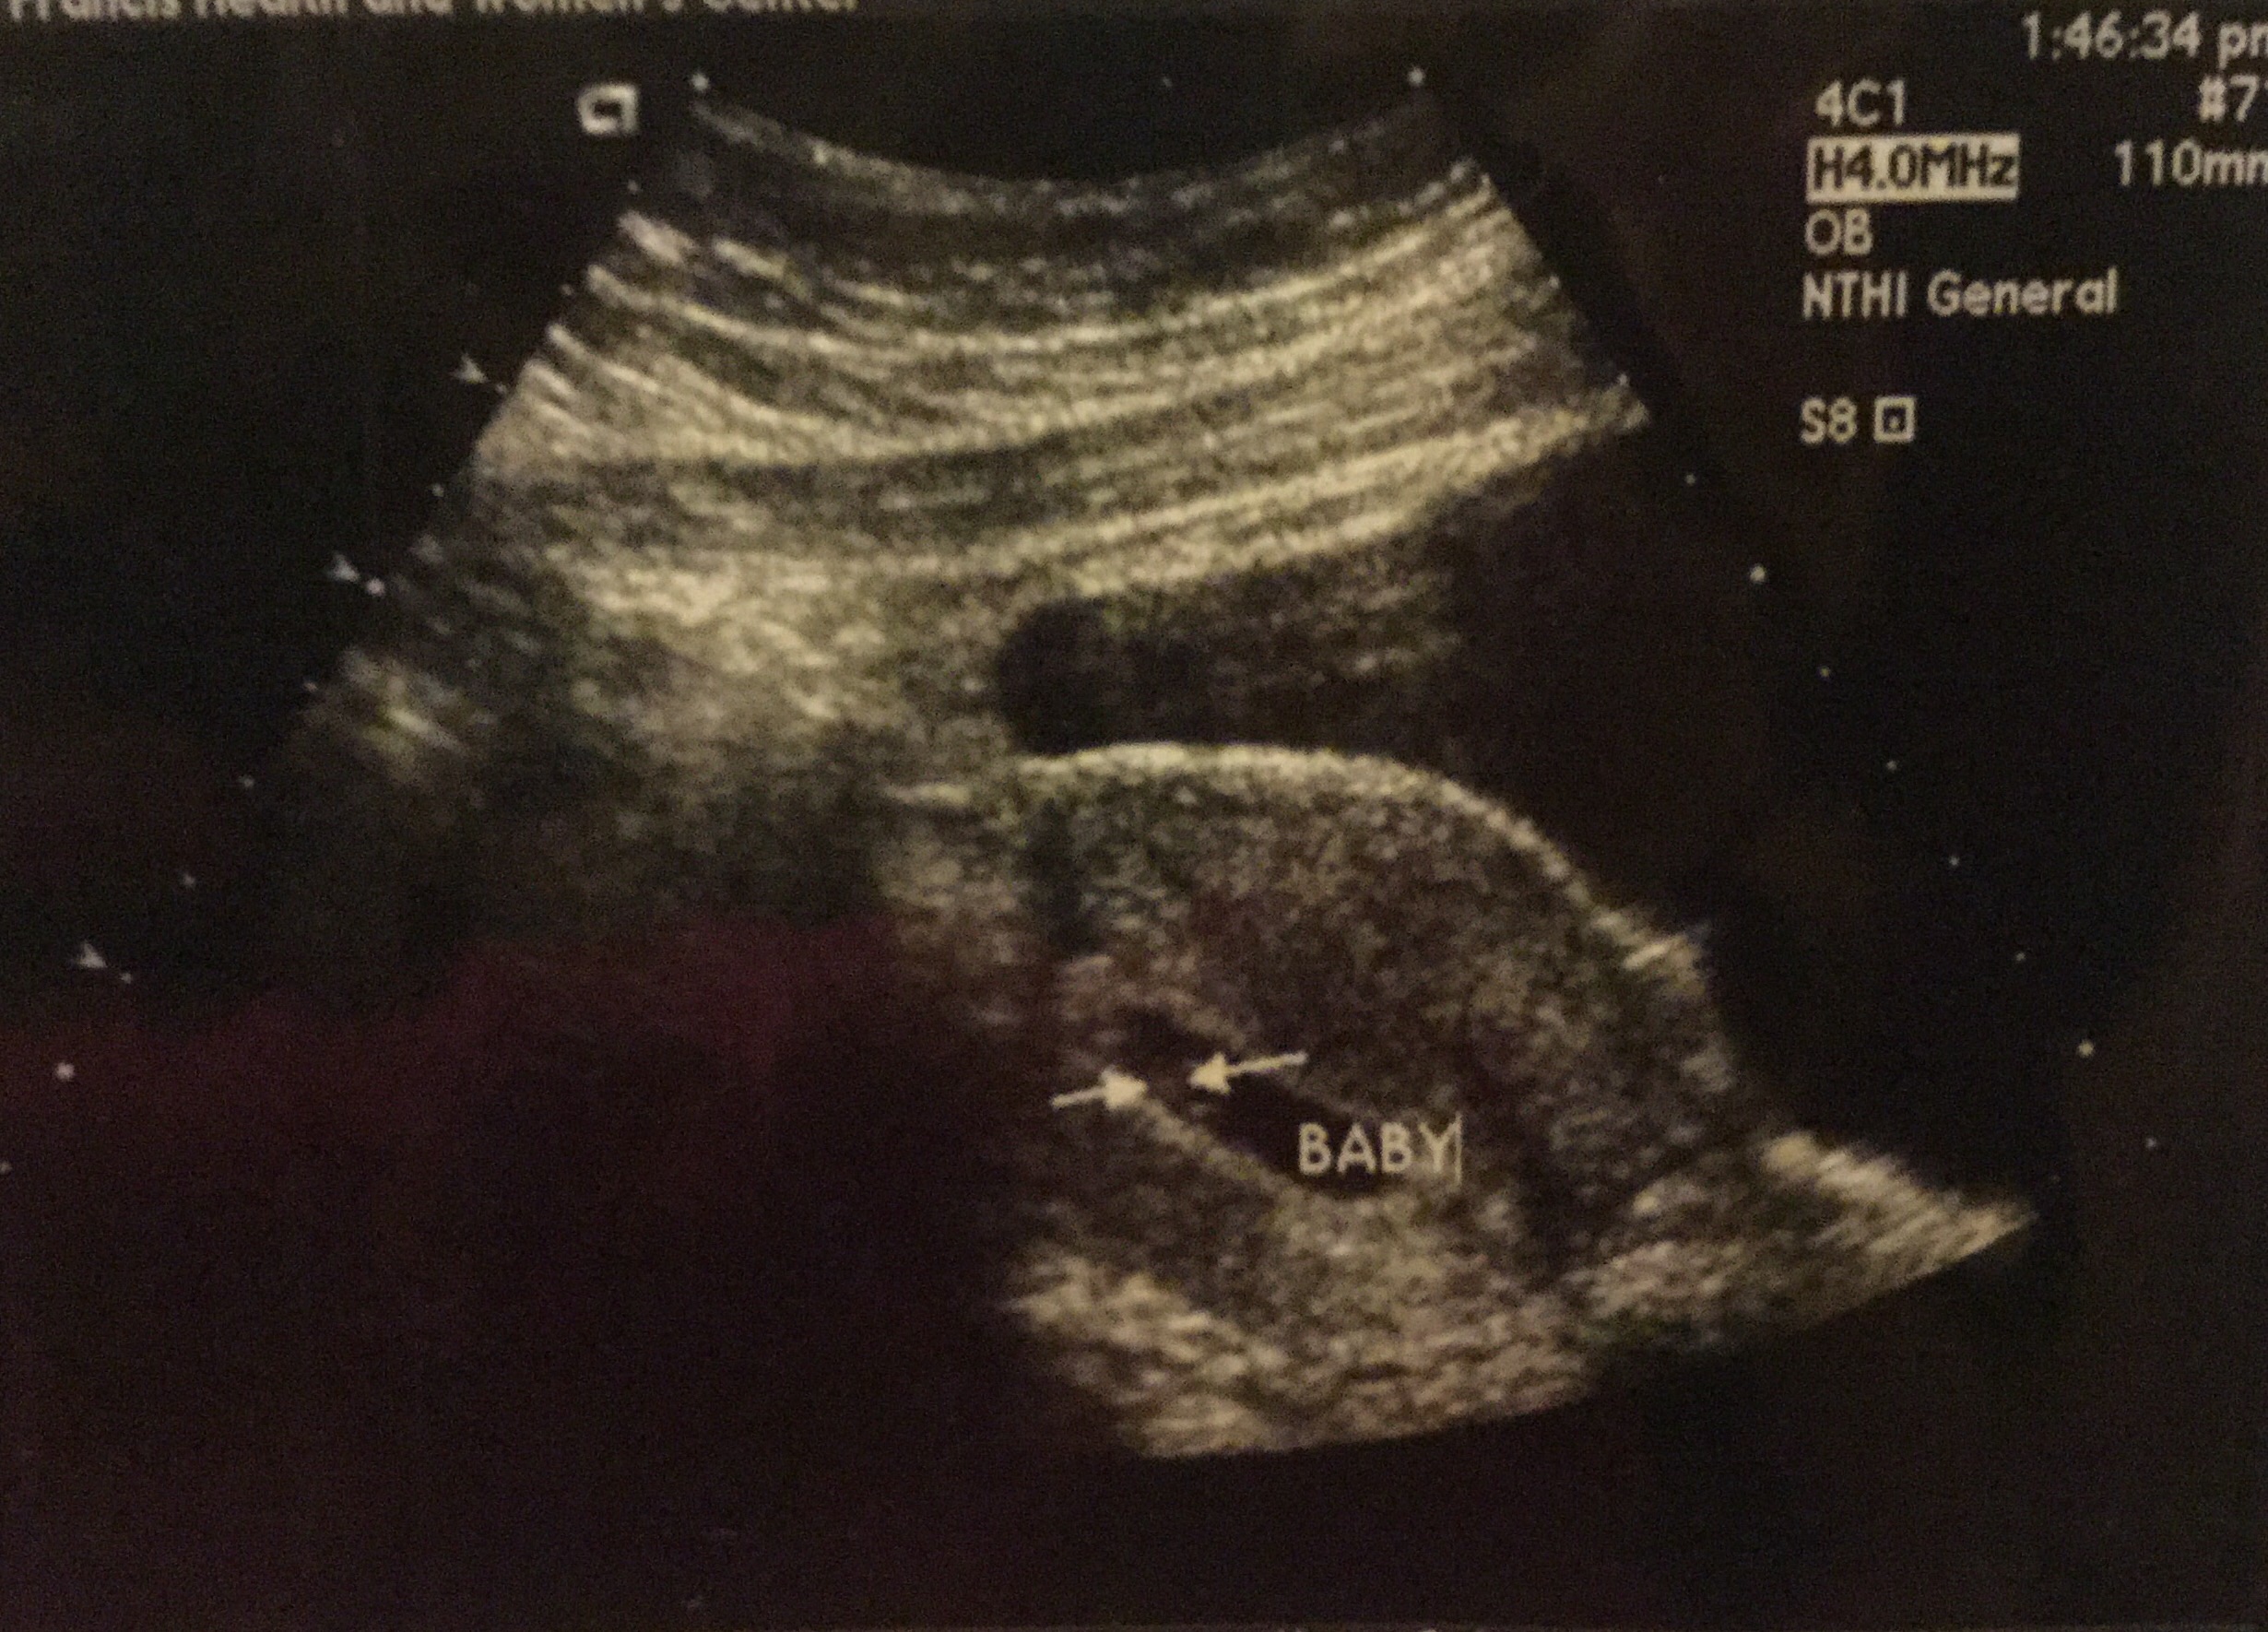

Finally got to see our peanut.

image

Apparently I cant figure out how to add a pic :)